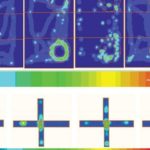

Immagine: una cellula staminale del cancro, prima e dopo il trattamento con composti di semi d’uva. Credit: Patrick Mansell.

I ricercatori riferiscono che se assunti separatamente a basse dosi, resveratrolo e estratto di semi d’uva non sono efficaci contro la soppressione delle cellule staminali del cancro, come quando sono somministrati in combinazione.

L’incidenza di tumori è stata soppressa nei topi trattati con i composti di uva del 50 per cento, un tasso simile al tasso del gruppo trattato con sulindac.